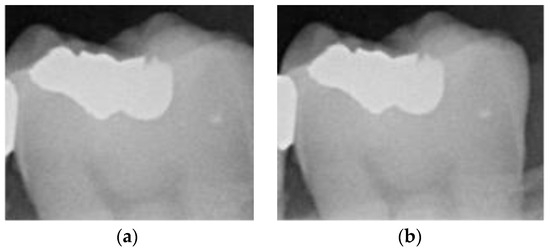

Figure 3.

Image-annotation step preserves edges on both sides of the tooth: (a) less of the tooth edge is retained; (b) more of the tooth edge is retained.